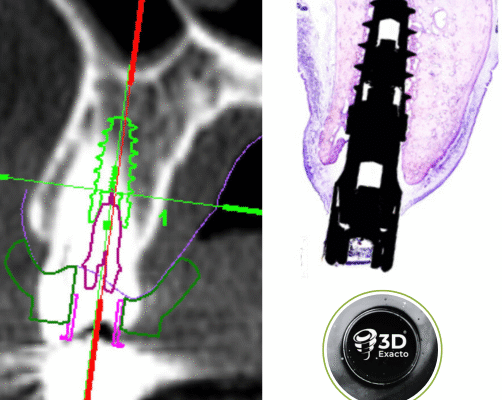

Cirugía Guiada por Ordenador

En nuestra clínica, ofrecemos cirugía guiada utilizando software 3D exacto, una técnica innovadora que nos permite planificar con precisión la colocación de los implantes y asegurar su correcta integración en el hueso maxilar o mandibular. De esta manera, podemos garantizar una colocación precisa, sin errores y con un mínimo de molestias para el paciente.

Durante la cirugía, se utilizan guías quirúrgicas personalizadas basadas en esta planificación digital. Estas guías ayudan a posicionar el implante en el lugar exacto determinado en la planificación, asegurando que esté perfectamente alineado y rodeado de suficiente hueso, lo cual es crucial para su integración y estabilidad a largo plazo. Además, esta precisión garantiza que el implante esté en la posición óptima para recibir la prótesis dental, lo que mejora la funcionalidad y estética del resultado final.